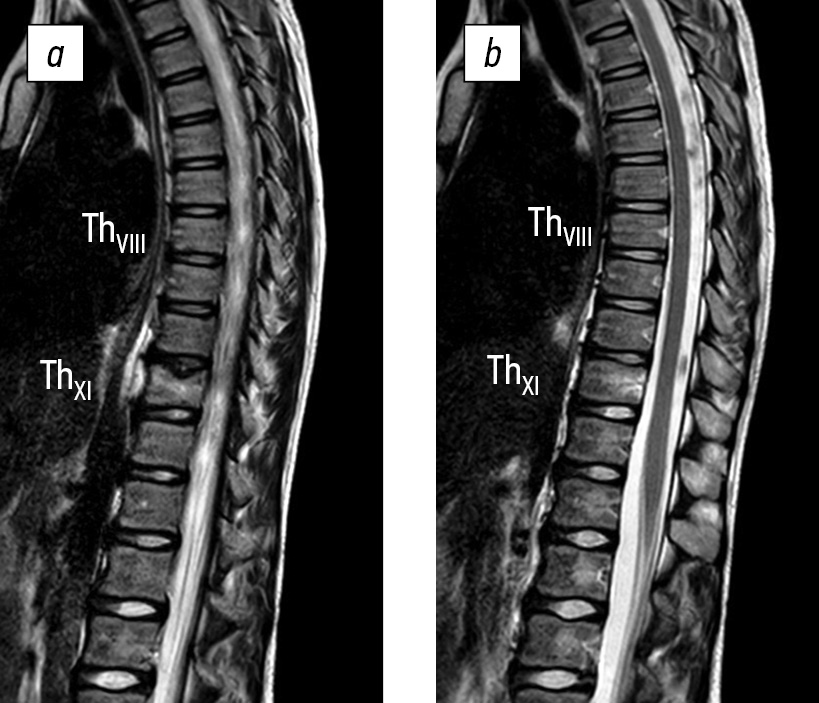

During the first visit to the Research Center, which occurred 2 months after the disease onset, an MRI review was conducted using T1-weighted imaging, T2-weighted imaging, and short-tau inversion recovery mode, supplemented with computed tomography (CT). The review revealed a lytic lesion of the ThXI vertebral body and a hyper-MR signal of the ThVIII vertebral body. The diagnosis was undifferentiated spondylitis. The patient was admitted to the Research Center’s department for further examination and trepanobiopsy with morphological verification of the condition (Fig. 1).

Fig. 1. Magnetic resonance (a) and computed (b) tomograms of the thoracolumbar spine with signs of spondylitis of ThVIII and ThXI vertebral bodies 2 months after disease onset (from the Turner Research Center for Pediatric Traumatology and Orthopedics’ archive)